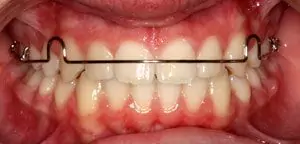

Removable Appliances

These are the appliances which are made of acrylic (tooth-coloured or pink) and can be worn and removed by the patients. These are usually used for minor teeth and jaw corrections. They are very aesthetic and they require to be worn for 24 hours by the patient. These are usually called plates and need activation or supervision by an orthodontist every 1 month or 15 days. At Smilex, a team of best orthodontists in Pune provides you with complete supervision and guidance with regards to your appliances.

Different Types of Removable Appliances

steel braces

If patient has minor spacing or crowding or mild proclination then removable plates can be given to correct such condition. But it does have its limitations while finishing the case.